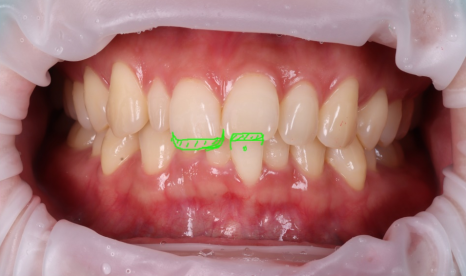

왜소치 레진으로 삭제 없이 자연스럽게 치료를 마쳤어요.

왜소치 레진이 끝난 뒤, 환자분이 거울을 보면서 바로 말씀하셨어요.

정말~ 감쪽같네요.

말씀드린 계획 중 첫 번째 방법으로 결정하셔서 앞니 레진 치료 후 아랫니 교합조정까지 해드렸어요.

이런 경우를 보면 앞니 치료는 한 부분만 보는 게 아니라 항상 전체를 같이 봐야 한다는 생각이 더 확고해져요.